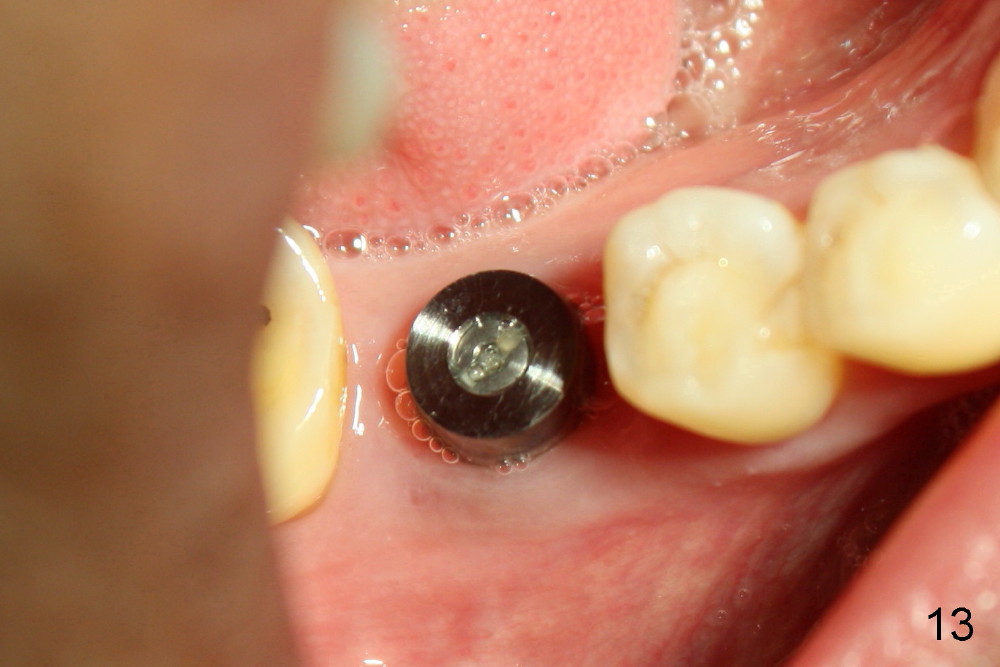

There is no atrophy of the buccal plate 2 months postop (Fig.13).